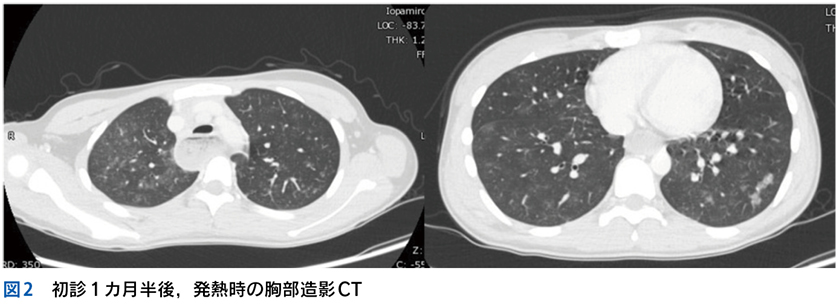

Case 1

独居の高齢者が自宅内で倒れている状態で発見され搬送された。最終健常は5日前。頻脈,SpO2低下,意識障害,感染徴候を伴う褥瘡,急性腎障害,高ナトリウム血症,クレアチンキナーゼ高値,炎症反応亢進,膿尿がみられている。

▶ この患者は何らかのイベントを契機に動けなくなり,長時間倒れていたものと推測される。多数ある「プロブレム」の中には,最初のイベントに直接起因するものもあるかもしれないが,大部分は倒れていた結果として生じてきたもの(最初のイベントの診断という観点では「ノイズ」)だろう。こういった患者が「脱水症」とか「横紋筋融解症」としてのみ治療されているケースをよく見かけるが,これは表層に現れた二次的,三次的な現象を取り上げているだけであり,最初のイベントの鑑別と治療が本来必要である。

Case 2

1カ月続く発熱と消耗のため入院している患者。発熱当初から変更を繰り返しながら抗菌薬が使用されており,現在も2剤併用中。ほかにも対症療法などで複数の薬剤を使用中。血液培養は抗菌薬使用開始後2週間で採取され陰性。経過中,皮疹,肝機能異常,腎障害,汎血球減少が出現している。

▶ こちらは初期評価不十分のまま多数の介入がなされたケースである。患者が呈している「プロブレム」をまとめて,「皮疹,肝機能異常,腎障害,汎血球減少を伴う遷延性発熱」とフレーミングし,たとえば血管内リンパ腫や血球貪食を伴う成人スティル病などを考えることも可能だが,現在の症状や検査異常(の一部)は抗菌薬をはじめとした介入の副作用として生じているのかもしれない。すべてのプロブレムが一元論で説明されない可能性も考慮したフレーミングも用意するのが謙虚な態度だろう。